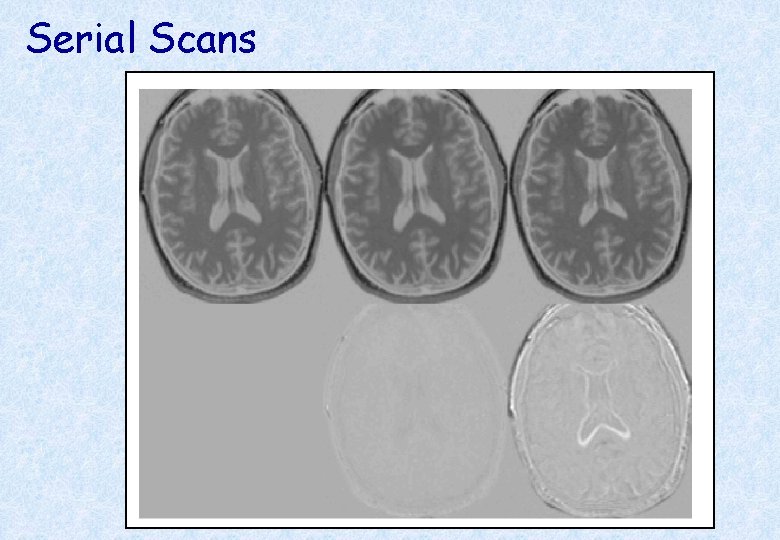

Serial Scans Early Late Difference Data from the Dementia Research Group, Queen Square.

Regions of expansion and contraction * Relative volumes encoded in Jacobian determinants.